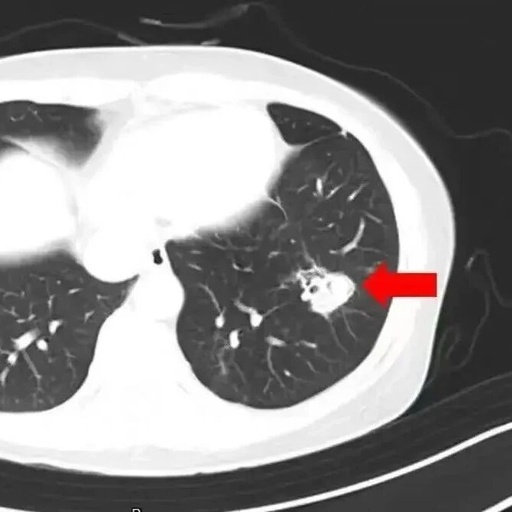

High Fever of 40°C After Spring Cleaning: Beware of Mold in the Lungs!

During the “May Day” holiday, how many people stayed at home to do a thorough cleaning? As the weather gradually warms up, many people take advantage of the clear skies to start organizing their wardrobes and making a “seasonal change”. Recently, Ms. Shen from Hangzhou took advantage of the good weather to rest at home … Read more